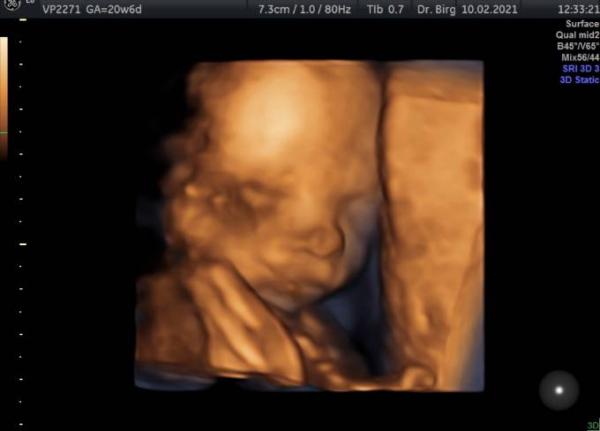

Hallo Ihr lieben. Ich war heute Mittag beim Organscreening. Alles ist bestens und sieht normal und gesund aus. Sehr kooperativ war der kleine leider nicht und hat sich immer nach hinten gedreht und die Hände vors Gesicht gehalten Sie konnte trotzdem alle wichtigen Organe sehen und beurteilen und wir haben trotzdem ein paar tolle Bilder bekommen und ich bin zufrieden und glücklich das alles passt. Das Geschlecht wurde auch nochmal definitiv bestätigt, aber das wussten wir ja im Prinzip sowieso schon ein paar Wochen. Er hat zur Zeit ca. 26.5 cm und hat 369 gramm